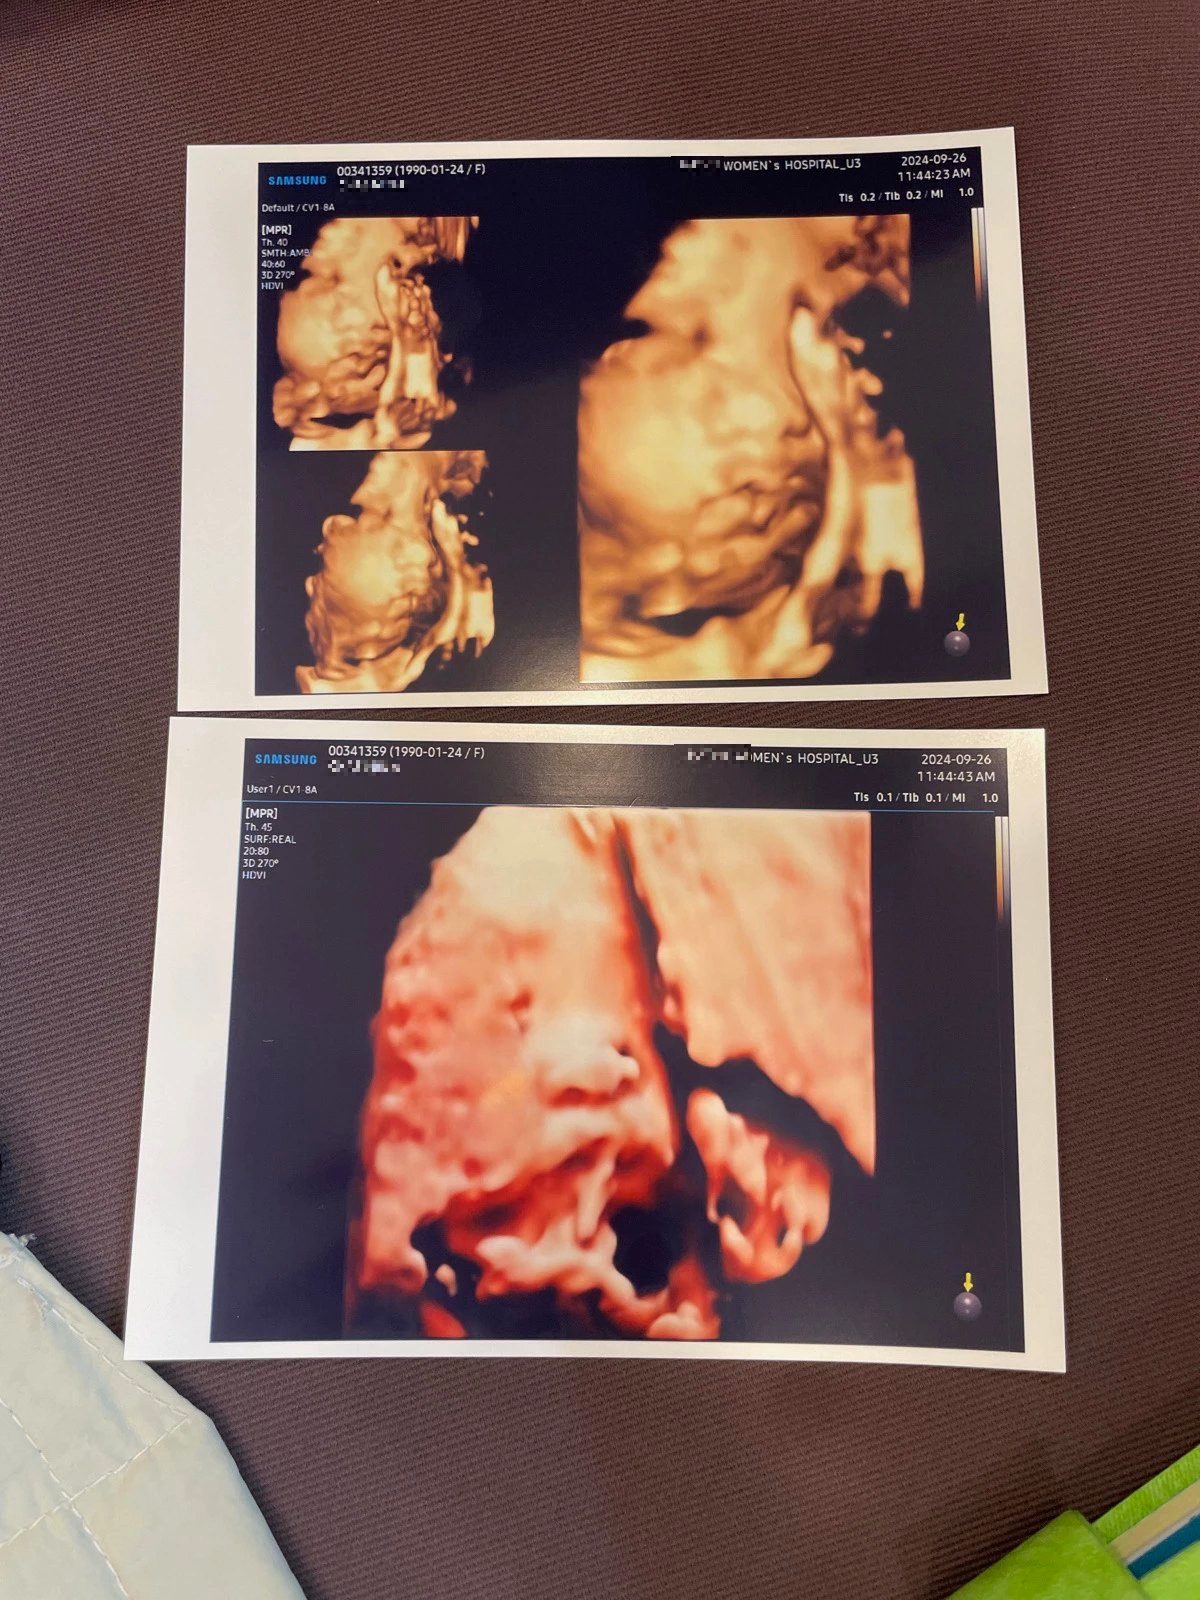

입체초음파 - 얼굴을 보여다오, 28주 3일

이제 얼굴의 윤곽이 어느 정도 보이게 되는 28주가 되어 입체초음파를 보러 갔다. 아기는 등원 보내고 둘이서 검진을 갔는데 이번 초음파 봐주시는 선생님이 엄청나게 꼼꼼하고 열심히 봐주셨다. 우리는 어느 정도 얼굴을 봤다고 생각했는데 얼굴이 제대로 안 보인다며 주치의 선생님 검진 끝나고 한번 더 봐주신다 했다. 그래도 여전히 잘 안 보여서... 다음 주에 다시 한번 보자고 하셨다. 이렇게까지 열심히 봐주신다고요? 감사합니다.

그래서 두 번째 입체초음파는 혼자 평일에 갔다. 다른 진료 없이 초음파만 보러 갔다. 여전히 명확하게 짠 하고 보여주지 않고 계속 손으로 얼굴을 가리고 있었지만 지난주보다는 어느 정도 잘 보여서 만족했다. 우리 부부가 워낙 닮아서 사실 둘째도 첫째와 비슷하게 나오지 않을까 생각이 든다. 첫째보다는 콧대가 조금 더 있어 보이는 것이 차이점이랄까? 아무렴 귀와 콧대와 머리숱은 아빠를 닮아주렴. 엄마는 속눈썹과 얼굴형을 닮아주렴. ㅎㅎ